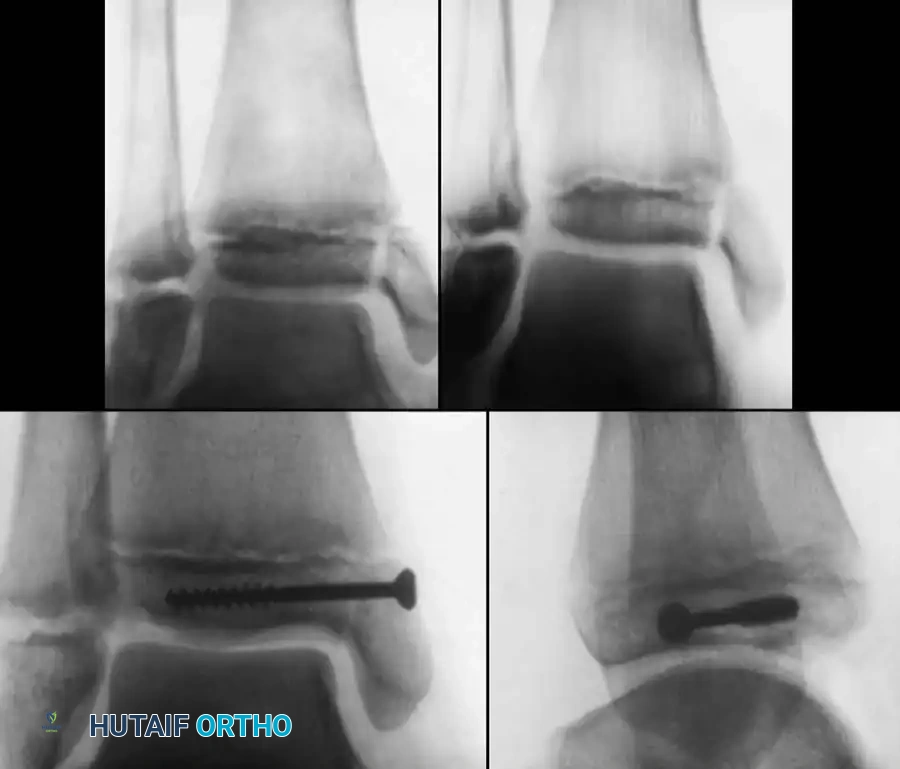

* Confirm joint congruity visually and via fluoroscopy.

Fluoroscopic confirmation of anatomic reduction prior to definitive fixation.

5. Fixation:

* For vertical fracture components, insert transverse guide pins.

* In older children and adolescents nearing skeletal maturity, utilize 4.0mm or 4.5mm partially threaded cancellous bone screws to achieve interfragmentary compression.

Final construct utilizing cancellous screws for rigid fixation.